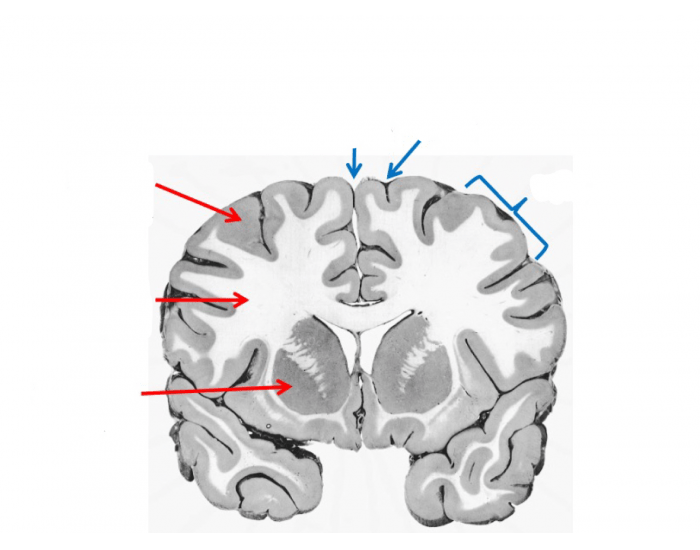

Cerebellum, brain region that coordinates sensory input with muscular responses, located below and behind the cerebral hemispheres and above the medulla oblongata. The cerebellum functions mainly in coordinating muscle activity for voluntary movements and in enabling fine muscle adjustments to maintain balance. The cerebellum is a vital component in the human brain as it plays a role in motor movement regulation and balance control. The cerebellum coordinates gait and maintains posture, controls muscle tone and voluntary muscle activity but is unable to initiate muscle contraction. Damage to this area in humans results in a loss in the ability to control fine movements, maintain posture, and motor Origin and location The cerebellum arises from the rhombencephalon or hindbrain. More specifically, it arises from the rhombic lips or alar plates (dorsal thickening of the neural tube that forms the sensory areas of the nervous system) of the metencephalon (spans between the pontine flexure and the rhombencephalic isthmus).. It is an ovoid structure that resides in the posterior cranial fossa

The cerebellum, which stands for "little brain" is a structure of the central nervous system. It has an important role in motor control, with cerebellar dysfunction often presenting with motor signs This article will focus on the anatomy of the cerebellum. It will provide a brief overview of its functions and development, and finally it